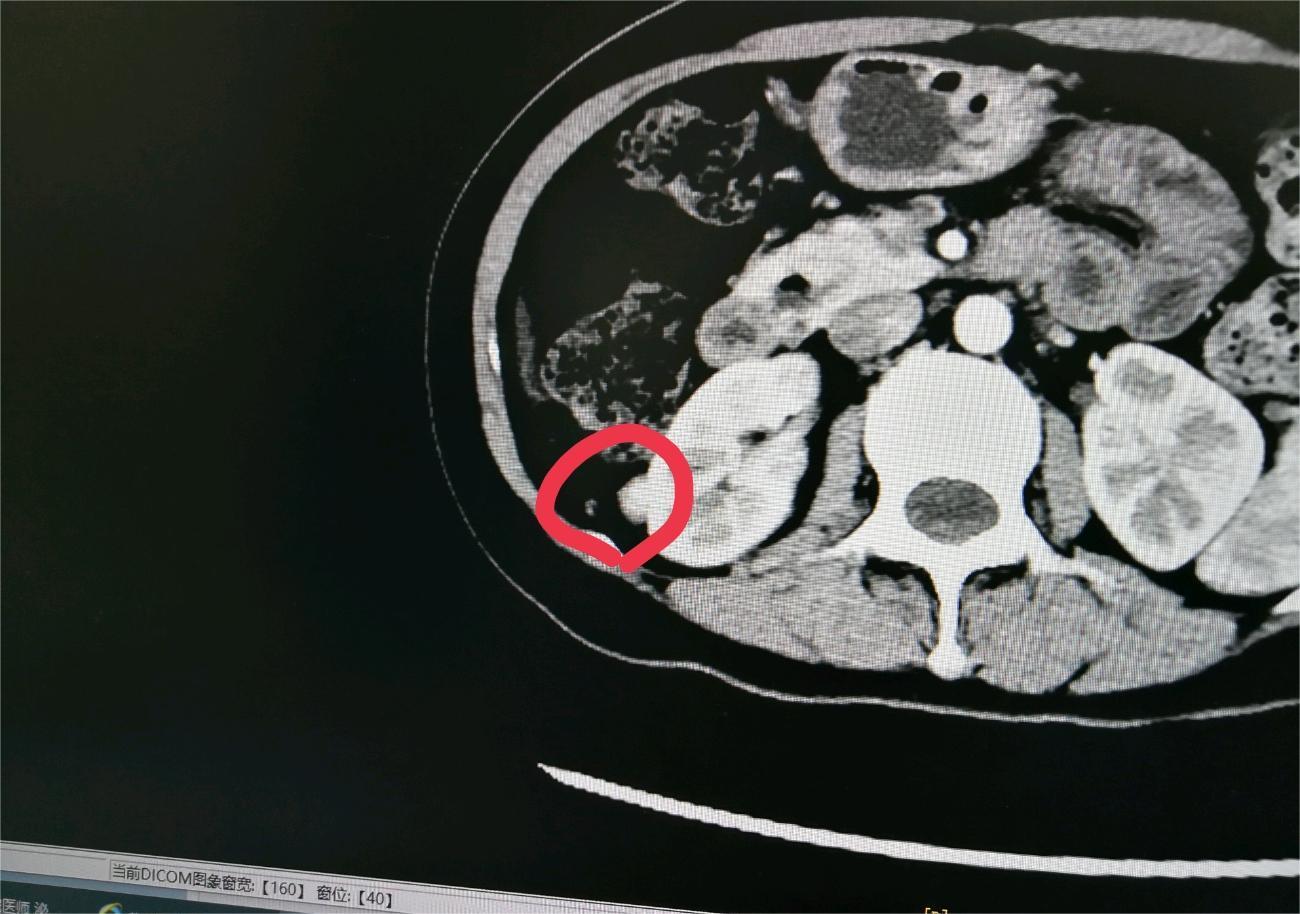

Here 02024-12-05 患者33岁,刚查出怀疑肾癌,麻烦有懂行的大神给分析一下,我是属于早期的吗?肾癌存活率是多少?有一个孩子,刚刚10个月。